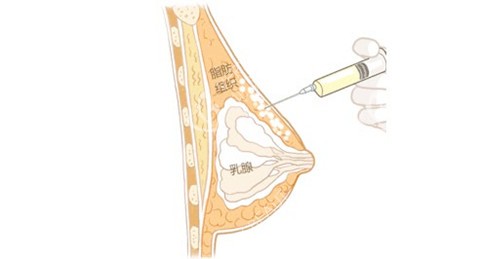

自体脂肪丰胸原理

自体脂肪丰胸是从自身肉多的部位,如大腿、腰腹部等抽取多余脂肪,经过筛选和处理后,再注射到胸部,让脂肪在胸部存活并形成稳定的脂肪组织,从而达到丰胸的结果。